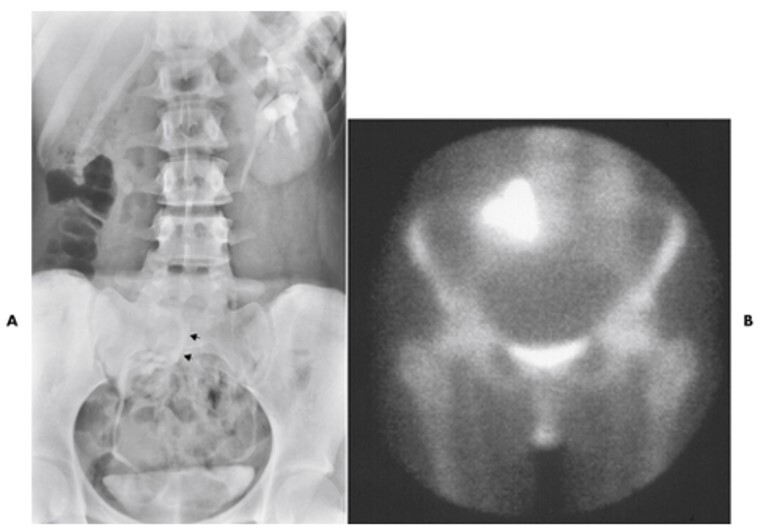

14

Q

What pathology is seen here?

A

Ureterocele